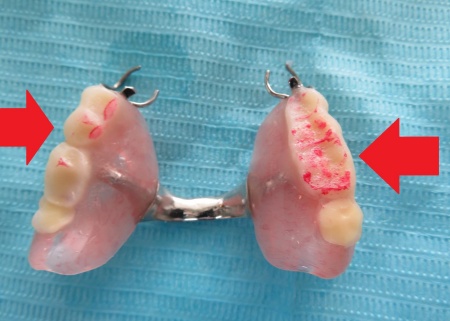

まず、入れ歯を装着した状態で噛み合う面に1mm程度、即時重合レジンと呼ばれる歯科用プラスチックを盛り、実際に噛んでいただきながら適切な噛み合わせの位置を慎重に確認して記録します。

プラスチックの硬化後は、はみ出した余分な部分を丁寧に削り取り、上下の歯が自然に噛み合うように調整を行いながら、表面を丁寧に研磨しました。

右側にもレジンを盛り、噛み合わせを記録します。